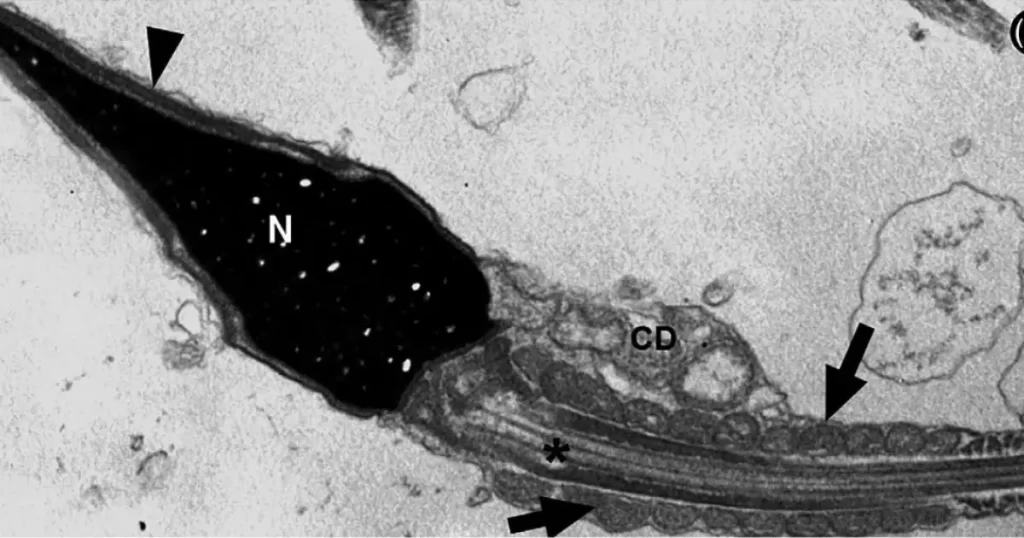

O vírus SARS-CoV-2 pode estar presente nos espermatozoides de pacientes até 90 dias após a alta hospitalar e até 110 dias após a infecção inicial, reduzindo a qualidade do sêmen. A constatação foi feita por pesquisadores da Universidade de São Paulo (USP). Mesmo outros estudos já relatando uma maior agressividade da doença para o trato genital masculino em comparação a outros vírus e, até mesmo, detectado o SARS-CoV-2 na gônada masculina durante autópsias, o patógeno dificilmente é identificado em exames de PCR do sêmen humano. Segundo publicação da Agência Fapesp, foram analisadas no levantamento as amostras de sêmen de 13 pacientes infectados e que desenvolveram COVID-19 nas formas leve, moderada e grave atendidos no Hospital das Clínicas da Faculdade de Medicina (HC-FM-USP), com idade entre 21 e 50 anos, em um período de até 90 dias após a alta e 110 dias após o diagnóstico. Mesmo todos testando negativo para a presença do SARS-CoV-2 no teste de PCR do sêmen, o vírus foi identificado em espermatozóides de oito dos 11 (72,7%) pacientes com doença moderada a grave até 90 dias após a alta hospitalar.